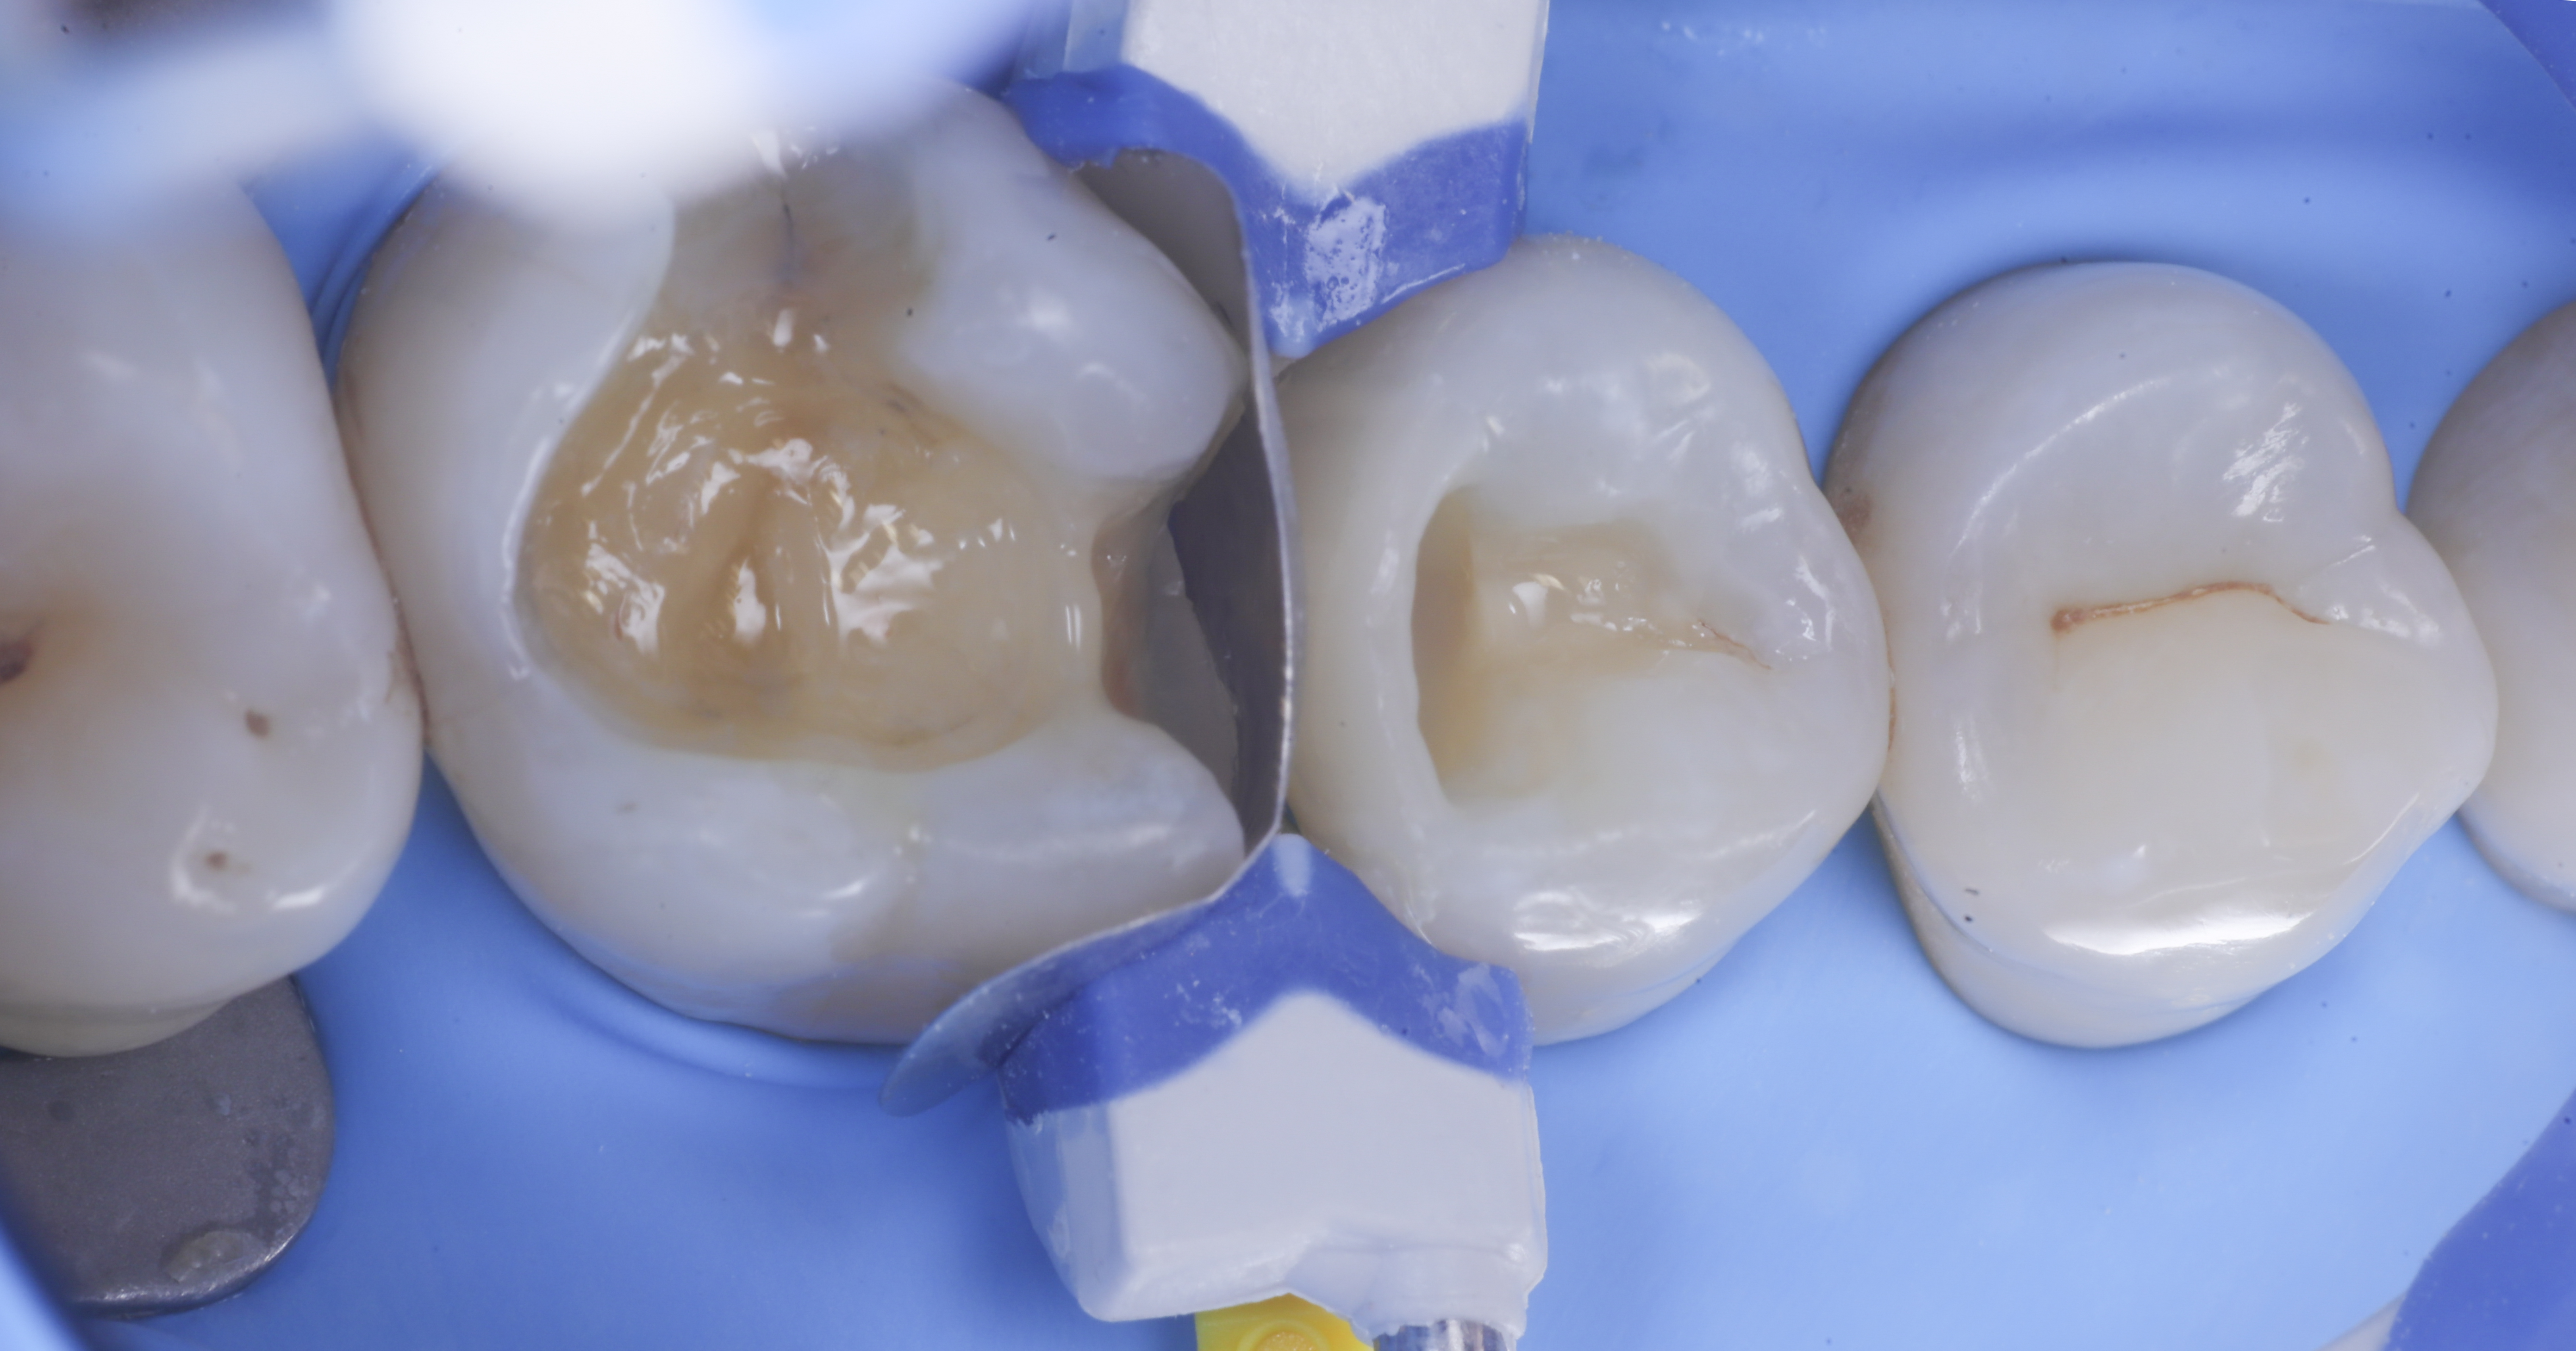

foto 4 Aspetto della chiusura cervicale e sulle pareti assiali dato dalla prima matrice

foto 5 Aspetto della chiusura cervicale e sulle pareti assiali della seconda matrice

Modellazione delle pareti inter-prossimali

A questo punto si procede con la stratificazione e modellazione di una delle due pareti inter-prossimali e si polimerizza. Si elimina quindi la matrice della parete appena eseguita sposando l’anello che viene immediatamente rialloggiato.

Successivamente, eliminato lo spessore dato dalla seconda matrice, si procede con la creazione della seconda parete.